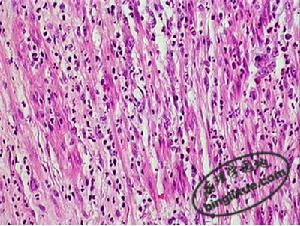

病理改變

病理變化主要位於肺間質、肺泡壁及終末細支氣管壁,有不規則的嗜酸粒細胞浸潤灶,有時肺泡內可見成堆的嗜酸粒細胞,極少累及血管。臨床表現